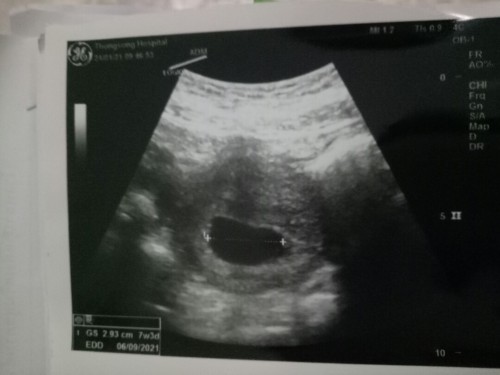

ยังไม่เห็นตัวอ่อน

เสี่ยงท้องลมไหม

อายุครรภ์เท่าไหร่คะ ตอนอัลตร้าซาวด์ บางคนอาจจะเจอตัวเด็กตอน 8-10 สัปดาห์ก็มีค่ะ

ของเราก็เป็นค่ะเราไปซาวตอน7wไม่เจอตัวอ่อนไปเจอตอน13+2wค่ะ